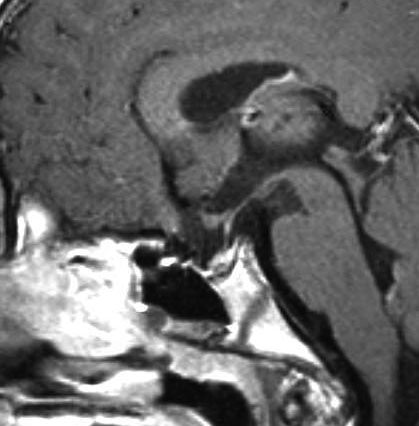

成人の第3脳室内部に局在する頭蓋咽頭腫です。経脳梁法で両側のモンロー孔から全摘出しました。下垂体組織は残っています。これは乳頭状頭蓋咽頭腫と呼ばれるもので,成人にしか発生しません,のう胞がなく石灰化もないのが大きな特徴です。境界が明瞭で柔らかく摘出が簡単なタイプとして知られています。この患者さんも術後に下垂体機能不全も視床下部障害も生じませんでした。